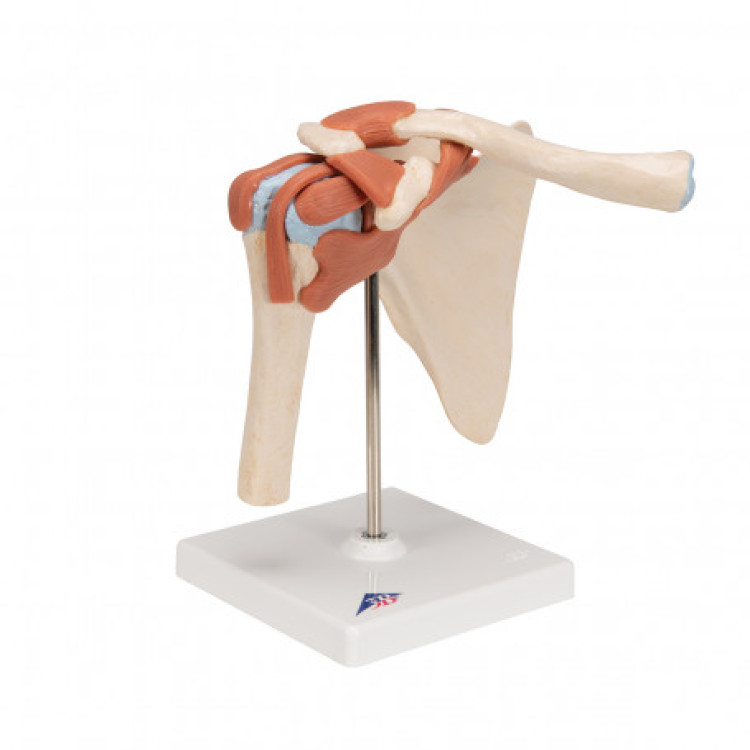

A80/1 Deluxe Functional Shoulder Joint Model

A80/1 Deluxe Functional Shoulder Joint Model

- Κωδικός προϊόντος: A80/1